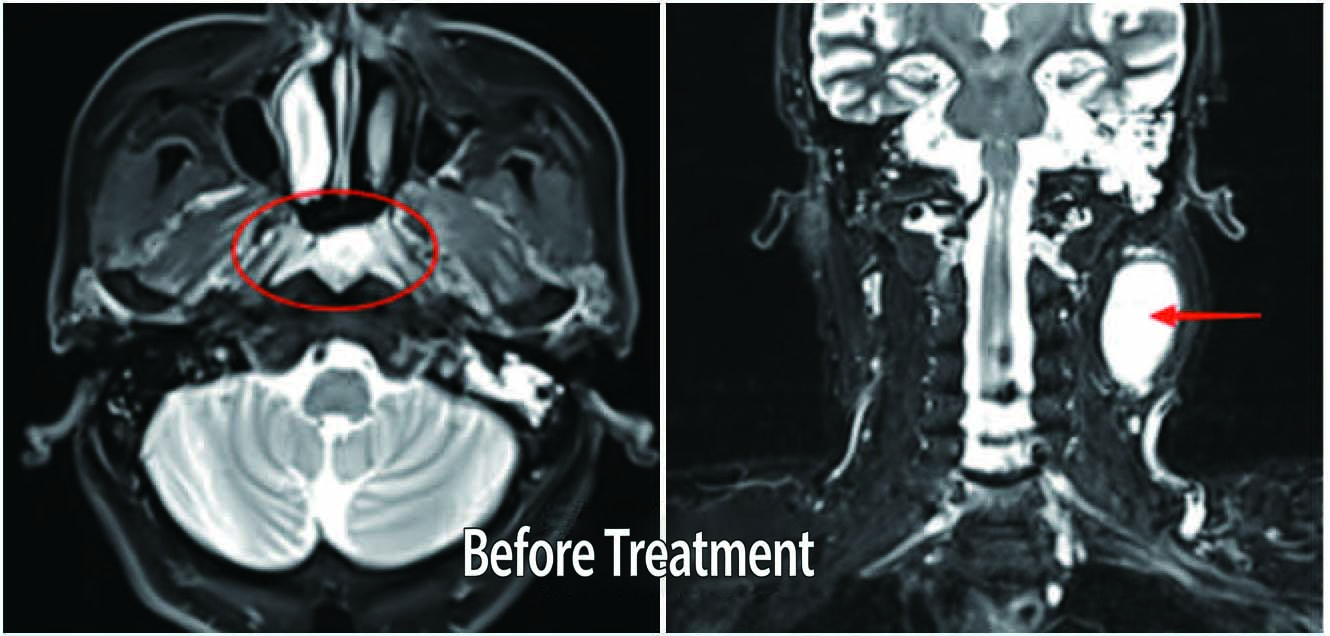

Before Treatment

Patient: Male, 66 years old

Diagnosis: Nasopharyngeal malignant tumor (Undifferentiated non-keratinizing carcinoma of nasopharynx) Treatment Period: April 12, 2021, to May 27, 2021

Treatment Modality: VMAT Radiotherapy (Prescribed dose to Planning Gross Tumor Volume: 69.96 Gy in 33 fractions, 2.12 Gy per fraction)

Outcome: After-treatment continuous follow-up examinations revealed gradual shrinkage of the nasopharyngeal mass.MRI results on January 5, 2023, showed complete disappearance of the nasopharyngeal mass, with significant reduction in previously positive lymph nodes.